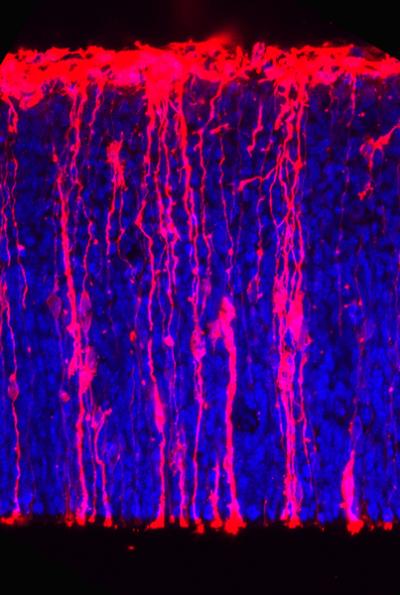

Brain neurons are generated from stem cells called basal progenitors that are able to proliferate in humans, but not in mice. In humans, basal progenitors are surrounded by a special environment, a so-called extracellular matrix (ECM), which is produced by the progenitors themselves. Like a cosy bed, it accommodates the proliferating cells. Mice lack such ECM, which means that they generate fewer neurons and have a smaller brain.

The scientists therefore conducted tests to see whether in mice, basal progenitors start to proliferate if a comparable cell environment is simulated. The result: "We simulated an extracellular matrix for the brain stem cells using a stimulating antibody. This antibody activates an integrin on the cell surface of basal progenitors and thus stimulates their proliferation", explains Denise Stenzel, who headed the experiments.